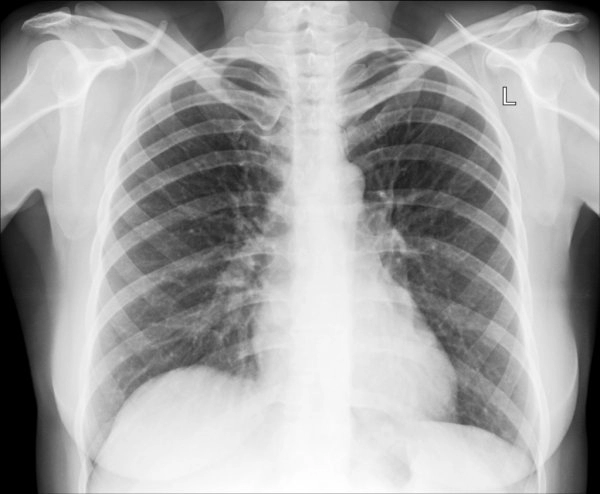

Рентген легких

Наиболее популярным методом исследования, используемым для диагностики заболеваний дыхательной системы, является рентген легких. Так называют процедуру, во время которой область грудной клетки просвечивают рентгеновскими лучами, а полученное изображение проецируют на фотопленку.

Благодаря тому, что ткани внутренних органов имеют различную плотность, на снимке хорошо видны уплотнения, очаги воспаления и другие патологии. Рентгеновские снимки позволяют выявить туберкулез, злокачественную опухоль, пневмонию, последствия травм, другие заболевания и состояния, требующие лечения.

Рентген легких в Москве является наиболее популярным видом диагностики благодаря своей доступности и информативности. Существует два основных метода: обзорный, когда делают снимки органа целиком, и прицельный, когда необходимо уделить внимание отдельным участкам легкого. Стандартное исследование выполняется в следующем порядке.

В диагностике заболеваний дыхательных органов рентген легких является одним из обязательных исследований, которое выполняют на начальном этапе лечения. Он позволяет обнаружить очаги воспаления и гнойные процессы, уплотнения в тканях, наличие полостей, в том числе заполненных жидкостью, патологические скопления воздуха (пневмоторакс), разрывы тканей, кровоизлияния, патологии легочных сосудов и др.

• Рентген легких показывает пневмонию?

При подозрении на пневмонию рентген легких является обязательной диагностической процедурой, которая показывает наличие участков затемнения или воспалительных очагов, а также состояние и структуру легочных тканей. В дальнейшем при необходимости могут быть назначены другие виды исследований.